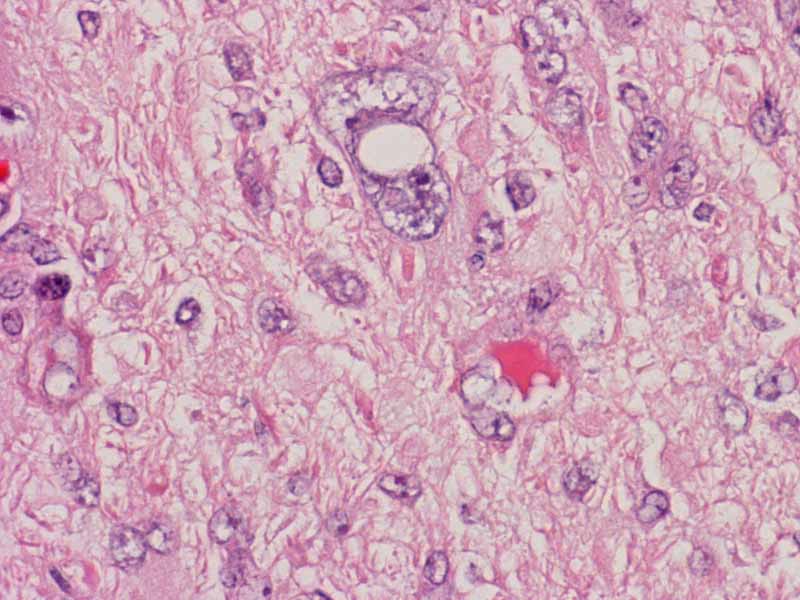

Hematoxylin & eosin

This image is taken from another slide of this case. In this area, the rhabdoid features are more prominent. Rhabdoid changes are featured by a large nuclei with prominent nucleoli. The cells is typically in an oval shape with a large belly of cytoplasm that pushes the nucleus to an eccentric location. Within the belly of cytoplasm is often a faintly defined inclusion body like body which may appear fibrillary on hematoxylin and eosin stain. This structure is composed largely of vimentin and will be strongly highlighted by immunohistochemistry for vimentin.